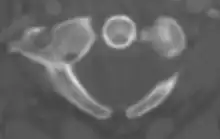

Atlas from above

The atlas's chief peculiarity is that it has no body,[3] which has fused with the next vertebra.[4] It is ring-like and consists of an anterior and a posterior arch and two lateral masses.

Vertebral foramen

Just below the medial margin of each superior facet is a small tubercle, for the attachment of the transverse atlantal ligament which stretches across the ring of the atlas and divides the vertebral foramen into two unequal parts:

- the anterior or smaller receiving the odontoid process of the axis

- the posterior transmitting the spinal cord (medulla spinalis) and its membranes

This part of the vertebral canal is of considerable size, much greater than is required for the accommodation of the spinal cord.